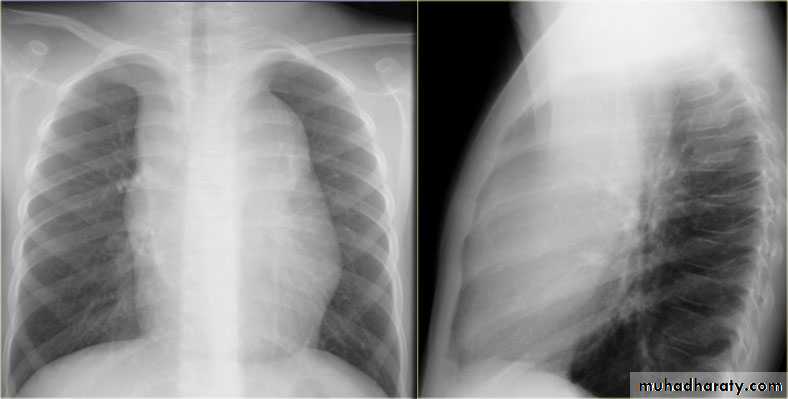

CXR of adult male PA and lateral views, it shows :Normal both lung fields ,Central cardiac shadow, Central trachea, central mediastinum, No boney lesions, no soft tissue abnormalitiesnormal radiologic anatomy of the chest Look carefully on both diaphragmatic cruse costo & cardio phrenic angles. Useful in detection of pleural effusion